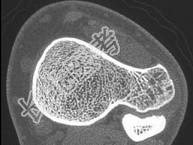

- 单项选择题青少年患者,踝部疼痛, 如图所示,最可能诊断为 ( )

A、软骨肉瘤

B、骨软骨瘤

C、转移瘤

D、骨肉瘤

E、以上都不是